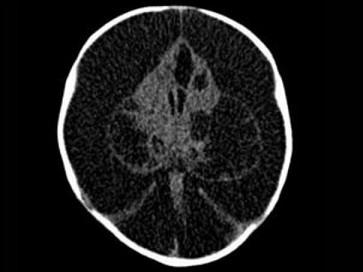

问题 3个月男婴,头颅迅速增大,发育停滞,CT表现如图,可能的诊断为 ( )

选项 A、先天性脑积水 B、重度脑积水 C、慢性双侧性巨大硬膜下血肿 D、水瘤 E、脑严重缺血

答案 A